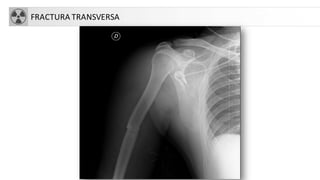

FRACTURA TRANSVERSA

FRACTURA HUMERO

• 5% de las fracturas del adulto, 75% en 1/3 superior

• Más frecuentes en ancianos (osteoporosis)

• Tratamiento:

• Conservador: cuello quirúrgico con impactación (ancianos)

• Quirúrgico: el resto

• Complicaciones

• Seudoartrosis

• Consolidación defectuosa

• Necrosis avascular

• Lesión nerviosa ó vascular

• Rigidez-capsulitis.

• Fx diáfisis: más frecuente en jóvenes o ancianos con fx patológica